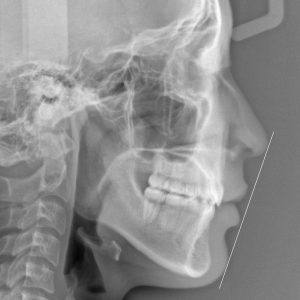

新着情報 1317 治療 後セファロ側面 – コピー Tweet 投稿日 : 2024年04月28日(日)カテゴリー : コメントを残す コメントをキャンセルメールアドレスが公開されることはありません。 * が付いている欄は必須項目ですコメント 名前 * メール * サイト 「 出っ歯、”すきっ歯” を 治してほしい」 16歳 女性 治療期間20か月(上顎前突症) ≫